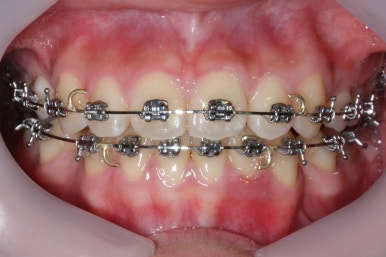

부산교정전문의 키다리아저씨치과에 처음 내원하셨을 때 당시의 입안 모습입니다.

윗니 뿐만 아니라 아랫니 부위에도 덧니가 관찰됩니다. 다른 앞니, 어금니 부위도 약간 삐뚤한 부분이 보입니다.